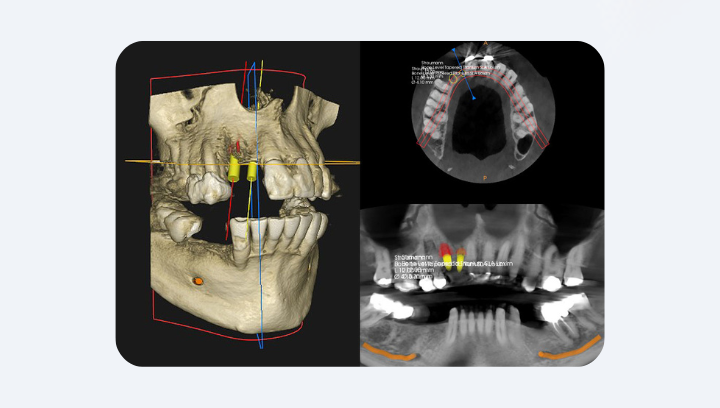

Имплантация

Планирование имплантации — это не только «выбор системы». Это анатомическая геометрия, где важна каждая десятая доля миллиметра. На панорамном снимке невозможно увидеть истинную толщину кости, её плотность или угол наклона гребня. А имплантат должен стоять в центре костной пластинки, не касаясь нерва и не перфорируя пазуху. КТ позволяет измерить высоту, ширину и плотность кости в вокселях (единицах объёма). Врач видит, где заканчивается компактная кость и начинается губчатая, а также расстояние до нижнечелюстного нерва — часто это 1–2 мм, которых на рентгене просто не существует.

Главное преимущество в том, что AXEOS и Orthophos — части единой экосистемы Dentsply Sirona. Они работают в связке с программами Sidexis 4, Galileos Implant, CEREC и inLab CAM, что позволяет создавать цифровые хирургические шаблоны для имплантации, планировать операцию в 3D с точностью до десятых долей миллиметра, совмещать КТ-снимок с интраоральным сканом для изготовления коронок и виниров без слепков, моделировать костные пластики и синус-лифтинг в виртуальном пространстве до операции.

Результат не нужно ждать несколько дней — он готов мгновенно. Врач открывает изображение в программе Sidexis 4, вращает модель в трёх плоскостях, показывает, как проходит нерв, где есть воспаление или почему нужна пластика кости. Пациент видит всё своими глазами — и это момент, когда страх сменяется пониманием. Если снимок делается для хирургии или имплантации, сразу создаётся цифровой план — модель, на которой врач определяет положение будущих имплантатов или разметку для навигационного шаблона.